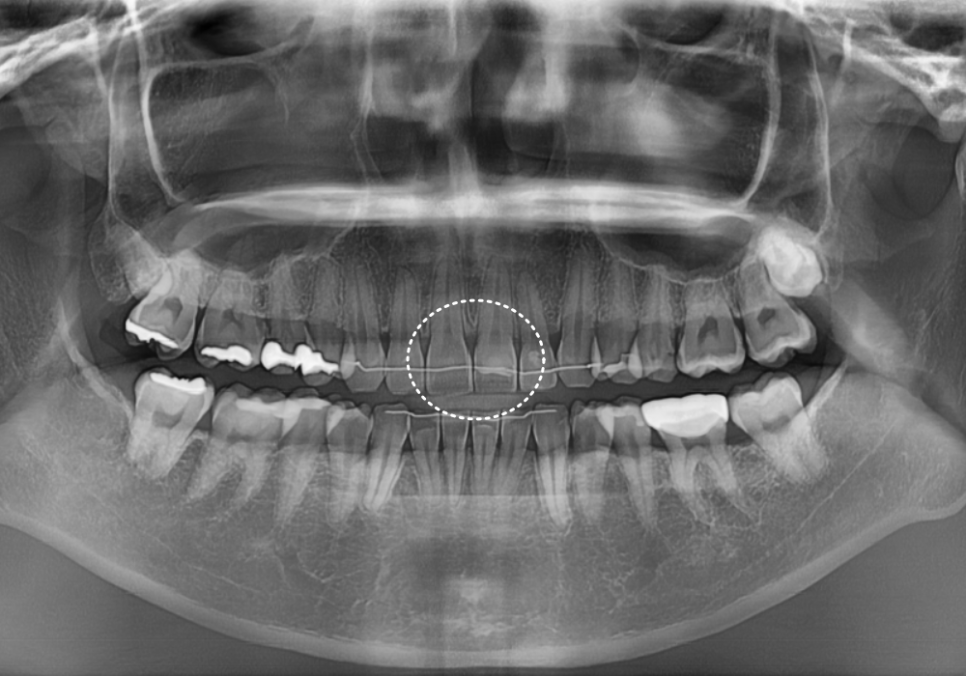

먼저 방사선 사진으로 확인해보니

다행히 2차 충치가 뚜렷하게 보이거나,

문제가 있어 보이지 않았습니다.

250726